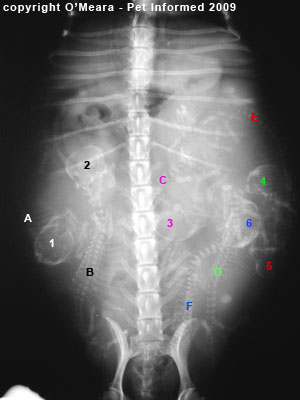

. X-ray imaging is a very important diagnostic tool. The cost can also vary depending on the location of the vets office. To evaluate respiratory conditions like asthma bronchitis and pneumonia heart conditions broken ribs and to look for fluid and tumors within the chest cavity.

X-rays may provide us with a needed diagnosis in other cases they may only provide clues or a few pieces to the puzzle of a cats overall health issues. X-rays of the chest or abdomen usually range from 100 250. If sedation or anesthesia is required for the x-rays this will be an additional fee.

The images are usually interpreted by the veterinarian who ordered the x-rays. Dental x-rays usually range from 75 to 150. It allows us to visualize structures within the body without the need for invasive procedures or surgery.